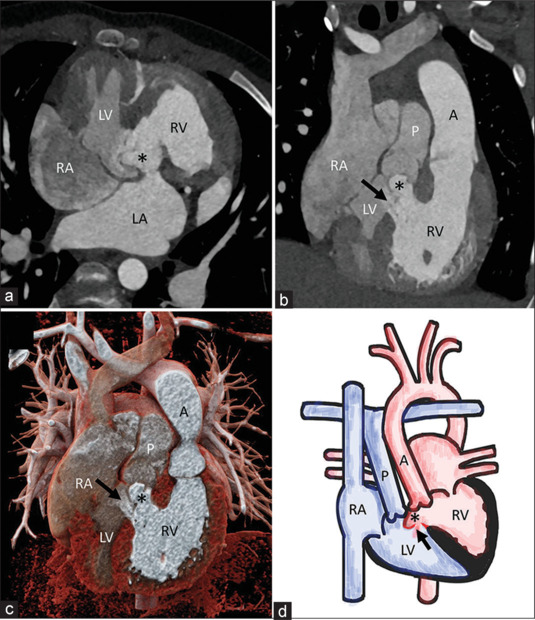

Ruptured Membranous Interventricular Septal Aneurysm Causing Left Ventricular Outflow Obstruction in Congenitally Corrected Transposition of Great Arteries.

先天性大动脉转位中膜性室间隔动脉瘤破裂引起左室流出梗阻。